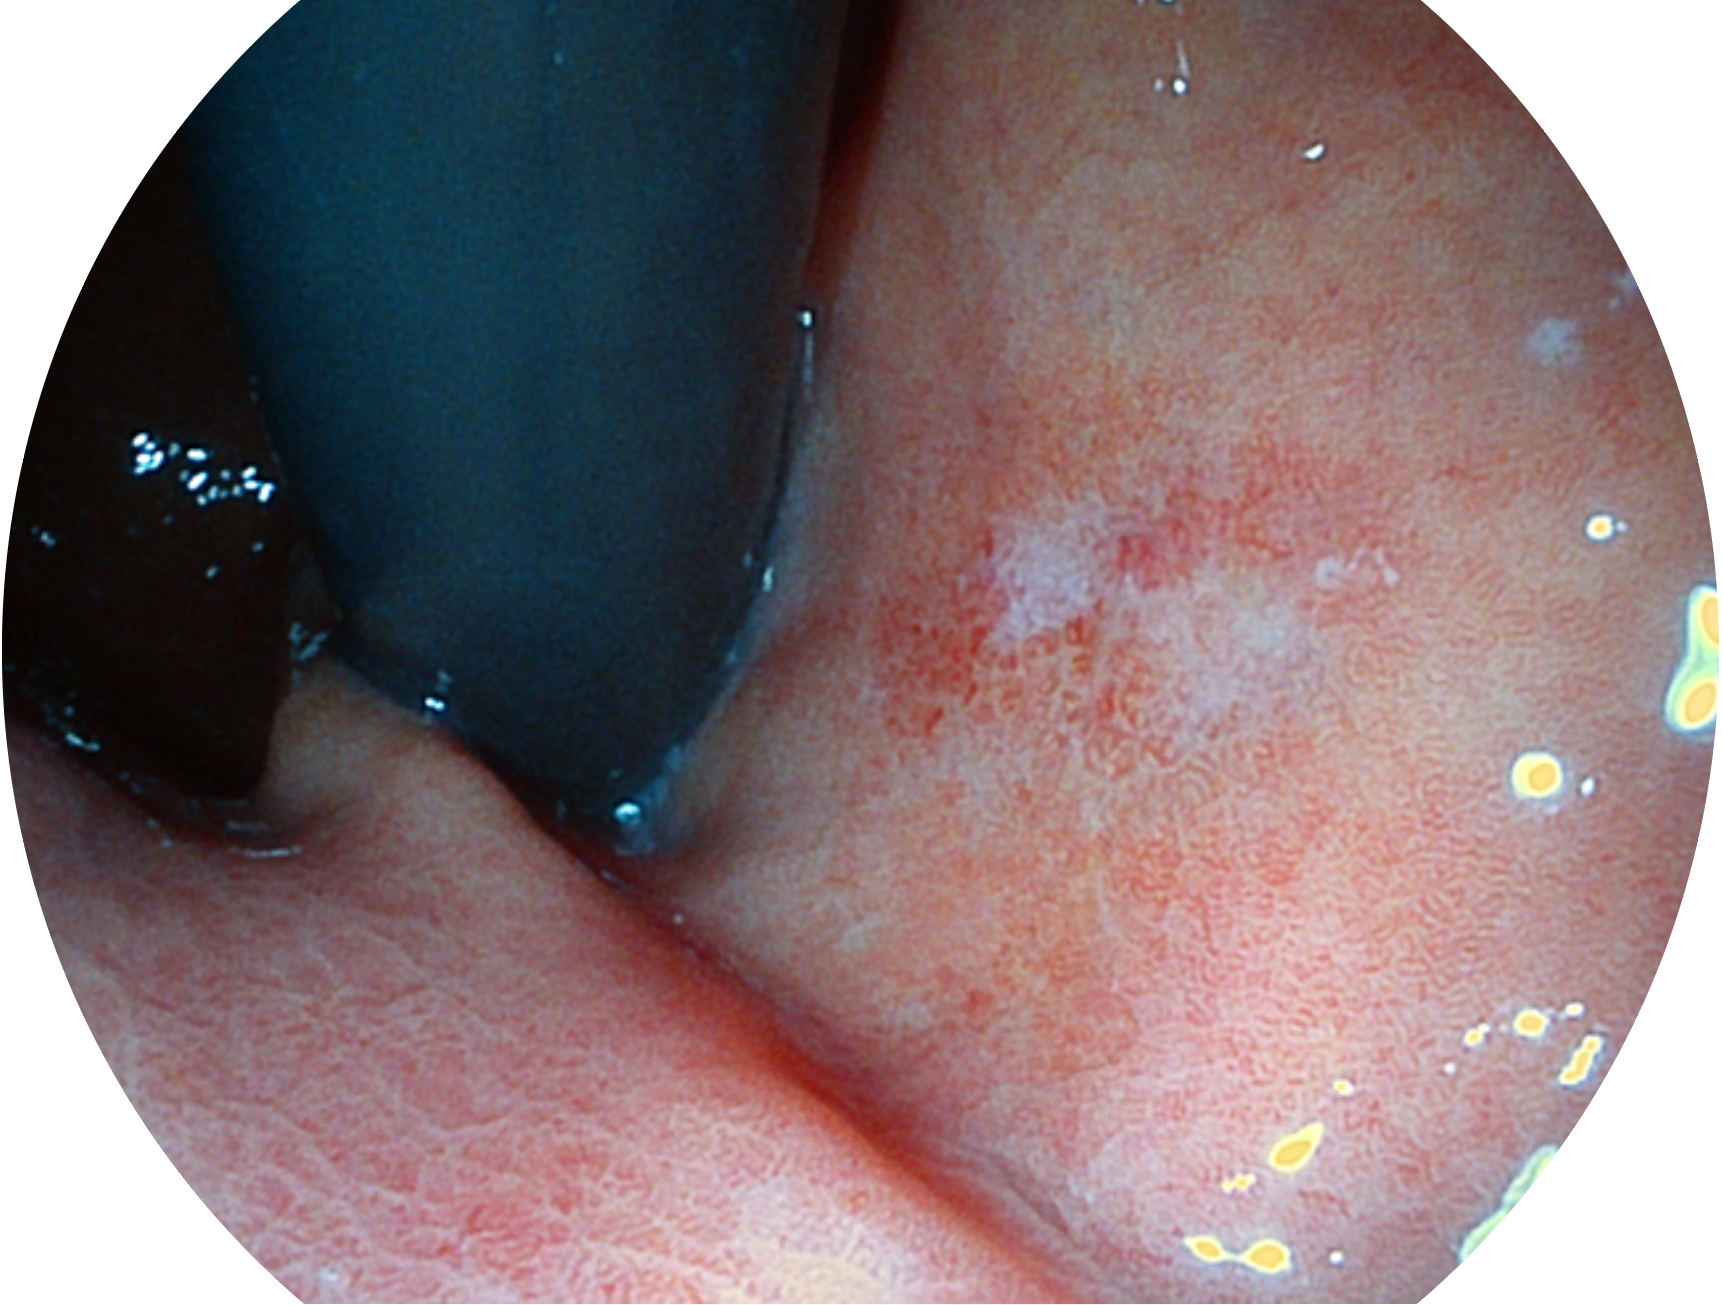

db真人体育官网新开发的内镜染色技术,主要是基于多波长LED 光源的开发,VLS-55Q 四波长LED 光源是由四个不同颜色的LED光按照相应照明模式所规定的特定发光比例进行合束后形成,合束后形成的照明光的光谱由红光、绿光、蓝光及蓝紫光这四个不同的波段范围构成。具有更高光谱自由度,通过光谱比例的控制,实现了聚谱成像技术,英文全称为“Spectral Focused Imaging, SFI”,缩写为“SFI”和光电复合染色成像技术,英文全称为“Versatile Intelligent Staining Technology, VIST”,缩写为“VIST”。